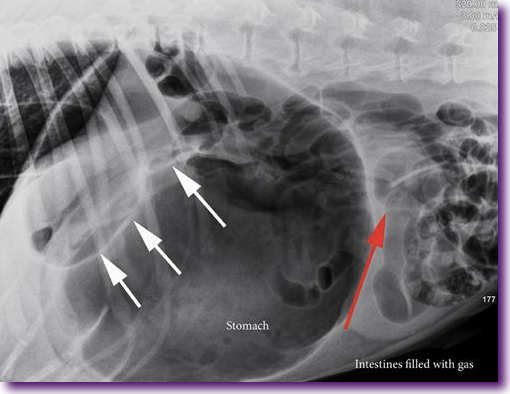

La torsión de estómago

La distensión del estómago se ve estimulada por el ingreso de aire en su interior (aerofagia), producido por varios motivos que aún están por aclarar desde el punto de vista veterinario. Es entonces cuando el estómago puede actuar como si fuera un globo lleno de aire o bien a modo de un caramelo envuelto en un papel, y girar en torno a su eje, torsionándose y comprometiendo la irrigación y el funcionamiento de dicho órgano. Los principales factores que parecen influir en que este hecho se produzca son la raza y la conformación física del perro, la alimentación y el estrés o el ejercicio físico.